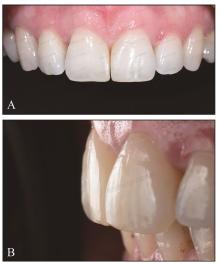

图 7

术后1周A:正面像;B:侧面像。"

图 8

术后1年A:正面像;B:腭面像。"